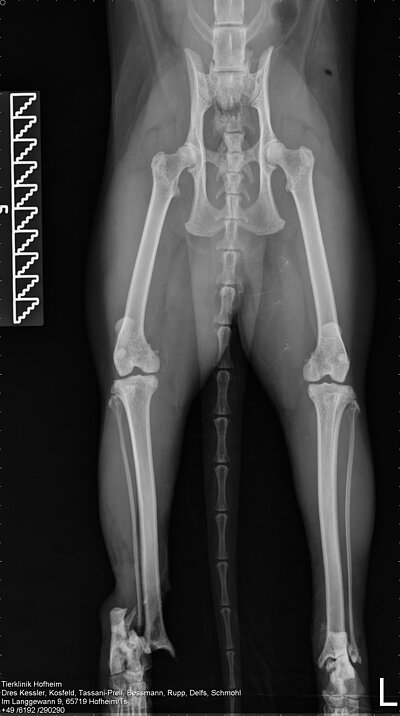

In einer ersten Operation wurde das Ausmaß der Verletzung erst richtig deutlich. Das rechte Sprunggelenk war eröffnet und luxiert, die Seitenbänder komplett zerstört. Das Weichteilgewebe war komplett abgeschliffen und hochgradig verschmutzt. Die Luxation wurde repositioniert und mittels eines Fixateur externe fixiert. Die tiefe Wunde am linken Hinterbein wurde gereinigt und soweit möglich verschlossen.